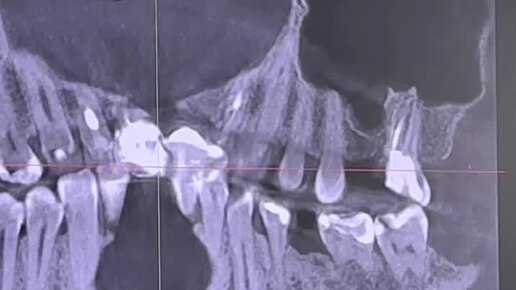

МИКРОСКОП LEICA M320 Лечение зубов под микроскопом

О здоровье простыми словами. Альфа-стоматология